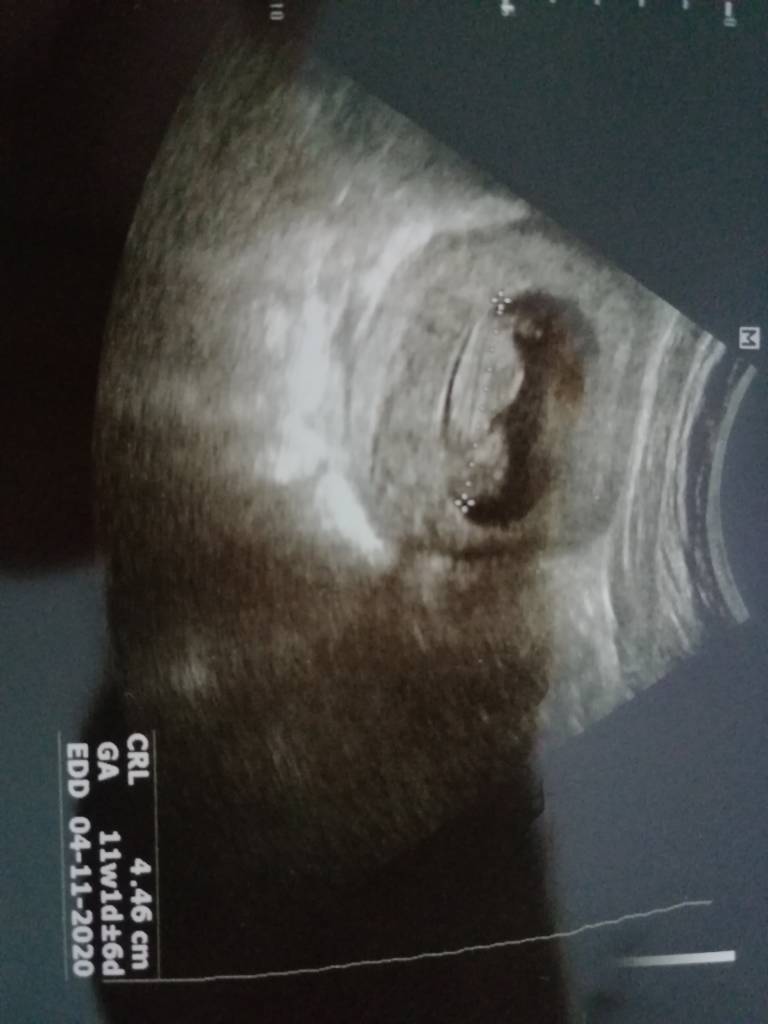

Ja byłam dziś na wizycie i dostałam urosept na te bakterie w moczu i skierowanie, żeby je powtórzyć po tych tabletkach a dzidziuś jakieś fikolki robi, najpierw był bokiem a jak lekarka głowice podniosła i znów przyłożyła to już tyłem dzidziuś się odwrócił, ale mówiła że dobrze bo zmierzy i zmierzyła najpierw 3.40 i wyszedł 10tydz a później tak fajnie podskoczył i na plecki się położył i głowke odgiął do tyłu i zmierzyla znowu i wyszło 4.46cm i 11tc +1 i już się wg tego zmieniła data na usg na 4.11 więc te daty to chyba z przymrużeniem oka trzeba traktować [emoji4]

USG dziś miałam przez brzuch i ładnie było widać dzidzie [emoji7][emoji3590]Zobacz załącznik 1106923